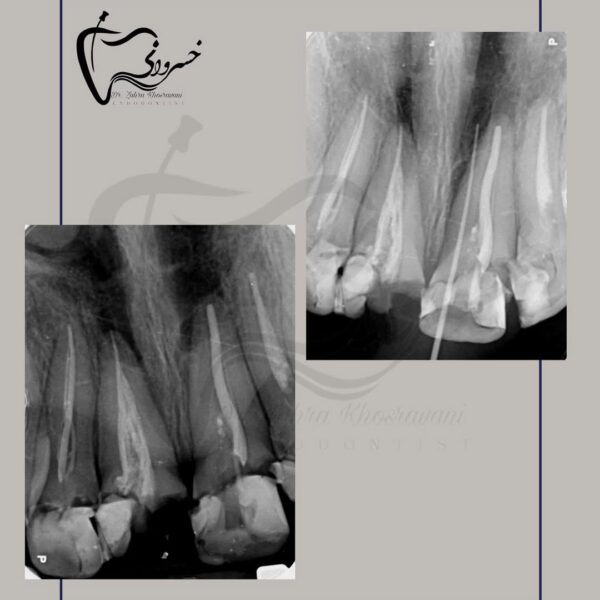

درمان ریشه دندان مولر اول پایه بریج

درمان ریشه مجدد

درمان ریشه مجدد دندان مولر دوم با ریشه رادیکس